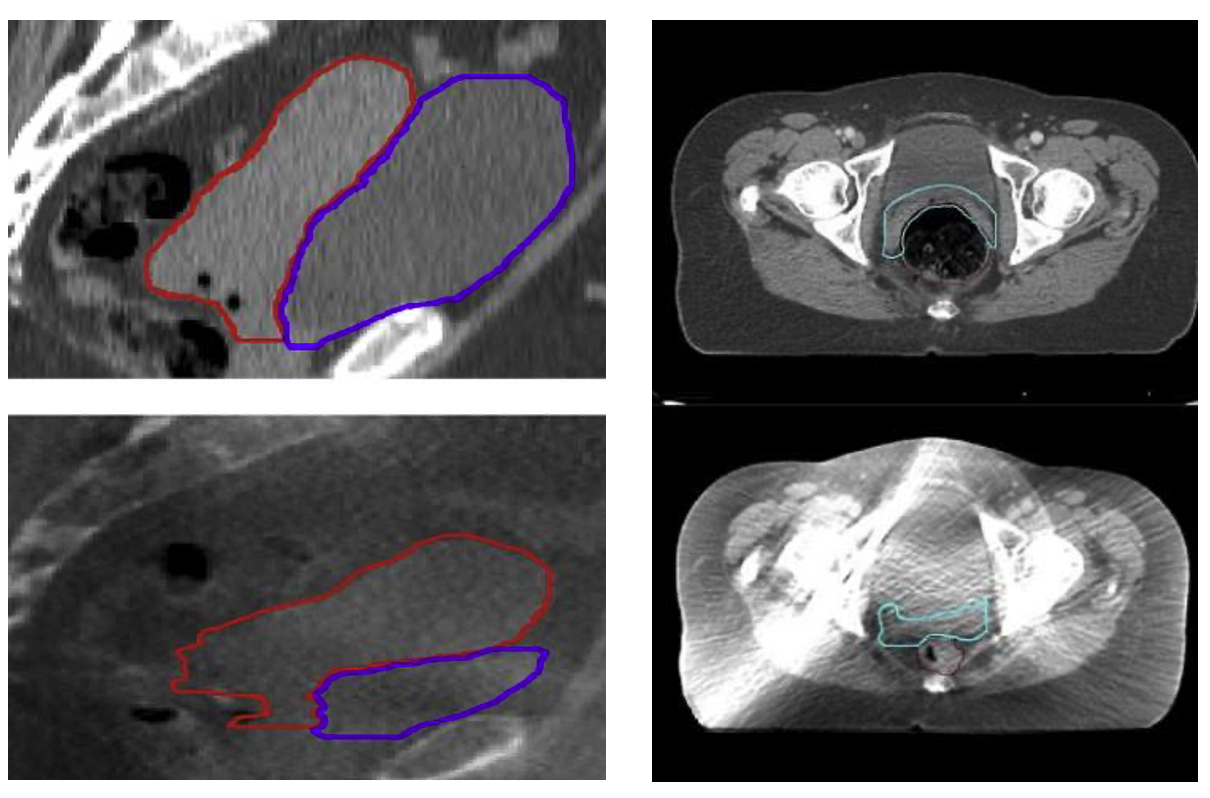

Förutom kliniska undersökningar, med angivande av tumörvolym i tre dimensioner (+ teckning), görs i dag MRT för bedömning av tumörstorlek och tumörutbredning både vid diagnos, ”pre-RT-MRT”, och inför brachyterapi, ”BT-MRT”. Marginalerna för targetvolymen bestäms med hänsyn till tumörkrympning.

MRT-undersökning spelar en avgörande roll vid bilddiagnostik inför en lyckad implementering av 3D brachyterapi vid livmoderhalscancer. Med överlägsen bildåtergivning av mjukvävnad visualiseras targetvolymer och riskorganen bättre. Apparatur, patientförberedelser och bildtagningsprotokoll behövs; se nedan och bilaga 2.

Gold standard för bildåtergivning är T2-viktade bilder med transversell, sagitell, coronal och oblique bildorientering. Para-axiala, sagitella och para-coronala bilder är orienterade utmed längsaxeln på cervikala applikatorn:

Figur 7. Hämtat ur: Dimopoulos et al, R&O, 2012 196

Vid repetitiva MRT-undersökningar bör samma bildåtergivning användas för att underlätta orientering och bedömning av tumörrespons under pågående strålbehandling. För applikatorrekonstruktion rekommenderas en para-transversell bildserie med 1–3 mm mellan snitten. Helst bör targetritning och applikatorrekonstruktion utföras på samma bildserie för att undvika osäkerhet vid fusion av bilder.